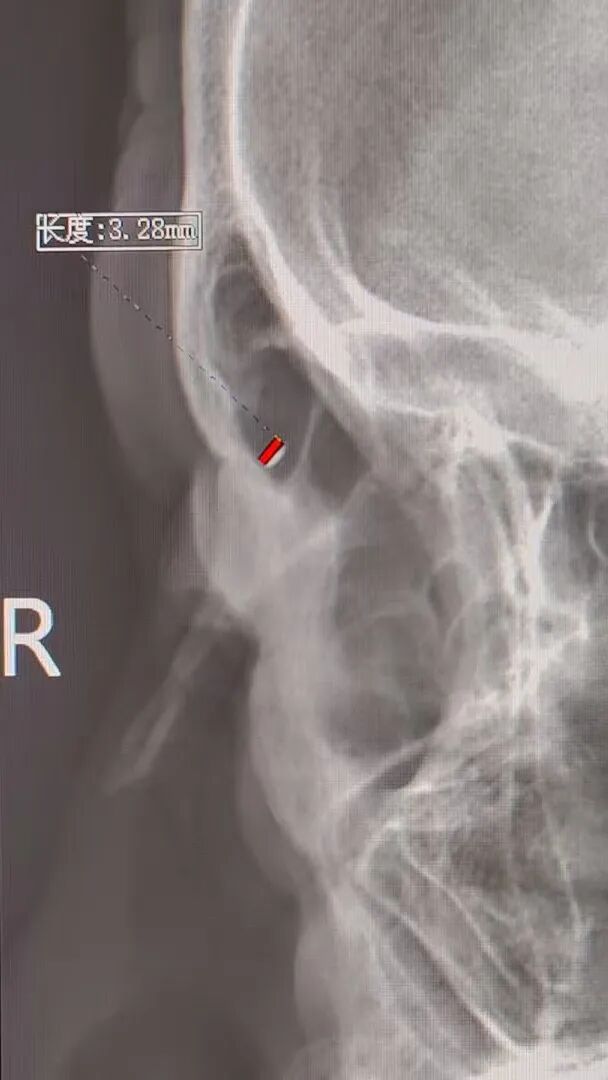

放射科曹俊涛医生接过“定位接力棒”:CT 擅长显示异物与周围组织的毗邻关系,X光片则能精准锁定空间位置。通过头颅正位片+右侧位片的联合检查,他不仅进一步确认了异物位于右眼两点钟方向,更精准测算出异物大小及与眼眶的距离,为手术提供了基础坐标。

“皮肤切口位置和探查深度仍是难点,出血可能影响术中判断,需要在皮肤面再做精确定位。”周医生带着患者转场超声科,超声科叶丹医生早已备好“秘密武器”,常规大探头对细小异物显示有限,我们的超高频小探头专门适配表浅细微结构。通过两个垂直方向的动态扫描,叶医生最终锁定异物位置,甚至精准测量出其与皮肤面的距离,为手术切口选择和探查路径提供了“精准导航”。